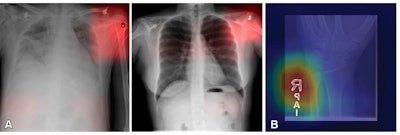

![Example of learning to make a diagnosis based on spurious correlation [e.g., laterality marker], rather than the disease or condition itself. (A) Images from a deep learning (DL) model in radiology that can learn to identify confounding features related to bias and unfair predictions, including laterality markers (image annotations indicate the side of the body being viewed [right vs left]) to identify the hospital at which a chest radiograph was obtained. (B) Image from a DL model that can make a diagnosis of radiographic abnormality on extremity radiographs, also known as shortcut learning. A. Images adapted and reprinted from reference 57, an open-source article, published under the Creative Commons license (CC BY 4.0). B. Reprinted, with permission, from reference 59. All courtesy of the RSNA.](https://img.auntminnie.com/mindful/smg/workspaces/default/uploads/2025/05/101148-radiol241674figure3.kYHaIAI5tS.png?auto=format%2Ccompress&fit=max&q=70&w=400) Example of learning to make a diagnosis based on spurious correlation [e.g., laterality marker], rather than the disease or condition itself. (A) Images from a deep learning (DL) model in radiology that can learn to identify confounding features related to bias and unfair predictions, including laterality markers (image annotations indicate the side of the body being viewed [right vs left]) to identify the hospital at which a chest radiograph was obtained. (B) Image from a DL model that can make a diagnosis of radiographic abnormality on extremity radiographs, also known as shortcut learning. A. Images adapted and reprinted from reference 57, an open-source article, published under the Creative Commons license (CC BY 4.0). B. Reprinted, with permission, from reference 59. All courtesy of the RSNA.

Example of learning to make a diagnosis based on spurious correlation [e.g., laterality marker], rather than the disease or condition itself. (A) Images from a deep learning (DL) model in radiology that can learn to identify confounding features related to bias and unfair predictions, including laterality markers (image annotations indicate the side of the body being viewed [right vs left]) to identify the hospital at which a chest radiograph was obtained. (B) Image from a DL model that can make a diagnosis of radiographic abnormality on extremity radiographs, also known as shortcut learning. A. Images adapted and reprinted from reference 57, an open-source article, published under the Creative Commons license (CC BY 4.0). B. Reprinted, with permission, from reference 59. All courtesy of the RSNA.